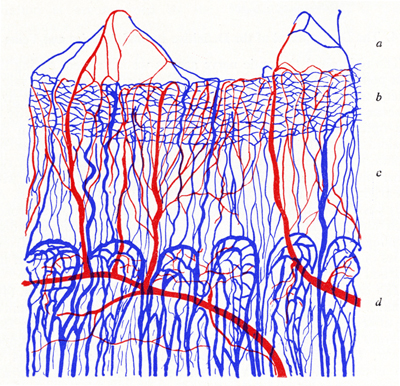

Vasos del Iris y del cuerpo ciliar en un feto humano de 290mm. a) Zona de las arcadas de la membrana pupilar b) Zona del esfínter pupilar con sus plexos. c) Vasos radiales arteriales y venosos del estroma iridiano. d) Procesos ciliares y ramos principales del circulo mayor

Foto tomada de: Ida Mann ; The development of the Human Eye. 1969. Grune & Straton Inc N.Y

Diagrama de la vascularización: 1- los vasos mas superficiales compuestos por arterias gruesas y venas contiguas en la parte central de la membrana pupilar formando las arcadas. 2- un conjunto mas profundo en el estroma. 3- Plejo de capilares ( ínter esfinterianos) en la sustancia del esfínter pupilar. 4- Plejo de capilares (sub esfiterianos entre el esfínter y el ep. pigmentario del iris.

Diagrama tomado de: Ida Mann ; The development of the Human Eye. 1969. Grune & Straton Inc N.Y